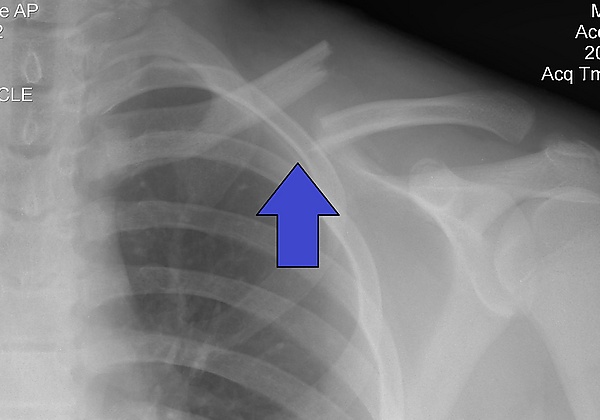

Перелом ключицы

Перелом ключицы — патологическое состояние, проявляющееся нарушением анатомической целостности ключицы. Чаще всего переломы происходят в средней трети на границе наружной и средней третей ключицы, на наиболее изогнутой и истончённой её части. Наиболее часто встречающиеся — косые и оскольчатые.

Составляет 2,6-12 % от всего числа переломов, 44-66 % переломов плечевого пояса. В 80 % случаев перелом происходит в средней трети, 15% — перелом акромиального конца ключицы, 5 % — стернального (грудинного).

Выполняется рентген в прямой и боковой проекциях.